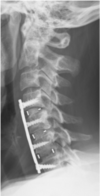

2 tx chirurgicaux en cas de scoliose

-Arthrodèse -Installation de tiges

C'est quoi l'Arthrodèse

Fusion des vertèbres par greffe osseuse et fixation interne en remplacement des disques intervertébraux

37

But de l'arthrodèse

Corriger la courbure

Quand utiliser l'arthrodèse (4)

-formes de scoliose les + graves (45 degrés et+) -Scolioses prises en charge trop tard -Idéalement en fin de croissance -Selon critères spécifiques de gravité